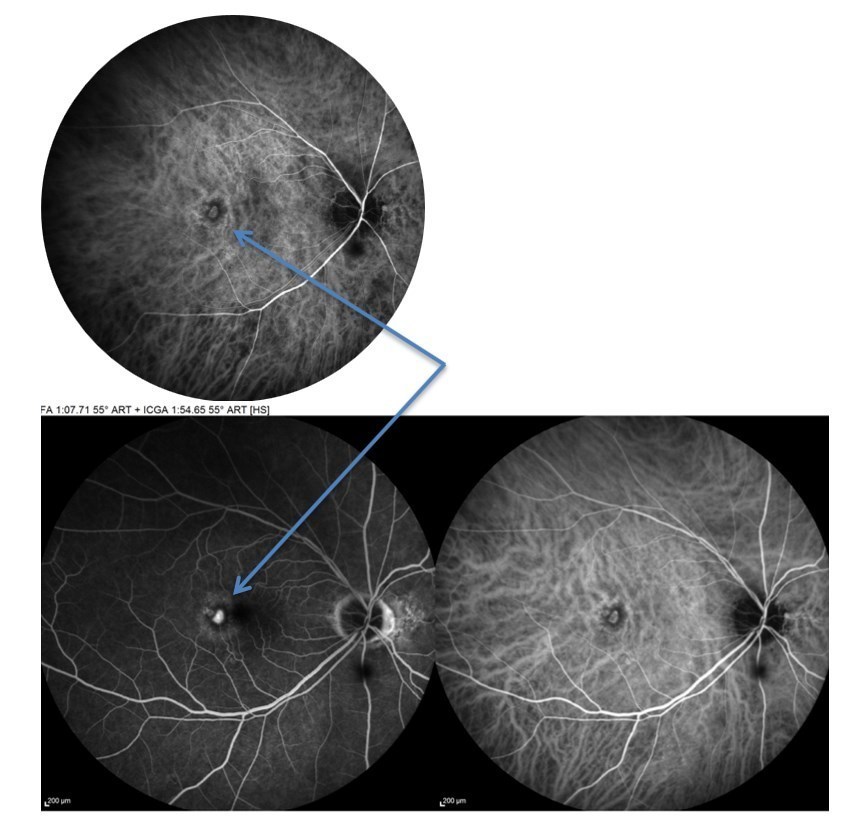

Voici les clichés de l’angiographie rétinienne à la fluorescéine et au vert d’indocyanine (ICG) :

Droite :

Gauche :

Question 6 : Concernant ces clichés d’angiographie rétinienne, quelles propositions sont exactes ?

Nouvelle question difficile dans ce dossier de DMLA, l’interprétation d’une angiographie rétinienne. Vous devez être stratégique et rester simple. A ce stade du dossier vous savez que vous êtes face à une DMLA exsudative, et que les néo vaisseaux de la DMLA sont d’origine choroïdienne. Vous devez donc retrouver une anomalie vasculaire à DROITE au moins en ICG, mais vu que ça saigne dans la rétine à l’OCT, cela signifie qu’on va également retrouver des anomalies en fluorescéine. Sur les 3 premiers clichés, on remarque cette lésion vasculaire rétrofovéolaire (flèche bleue) qui s’imprègne de colorant et qui n’a rien à faire ici (Si vous connaissez par cœur votre collège des enseignant d’Ophtalmologie, vous savez donc que la fovéa est une région anatomique AVASCULAIRE). Donc cette lésion en ICG, qui diffuse également très nettement en fluorescéine est totalement anormale et représente le néovaisseau choroïdien qui a réussi à soulever l’épithélium pigmentaire ET à le transpercer pour saigner directement dans la rétine. Avec de l’entrainement vous serez plus à l’aise avec cette notion.